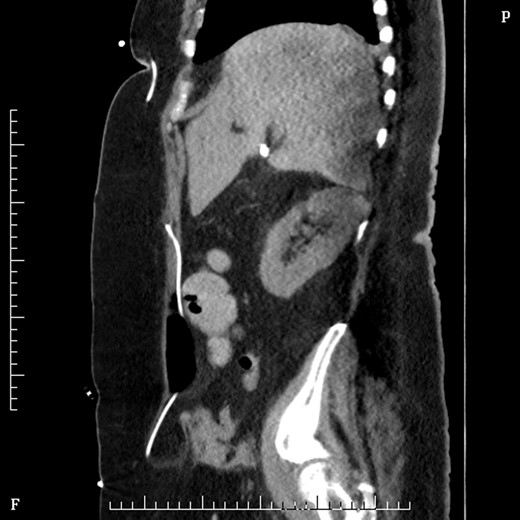

On Day 2 post VP shunt insertion, she was noted to be slow to recover and CT abdomen was performed. This demonstrated that the distal catheter tip was not in the pleural space but entered the abdomen and was redirected out along a tract into an umbilical hernia (Fig. 5). The following day she was taken back to theatre and the VP shunt was revised, and good visualization into the abdomen gave the impression that it was correctly in place. Repeat CT abdomen was performed to confirm placement and to our surprise the catheter had re-entered the same tract and travelled into the umbilical hernia (Fig. 6).

Sagittal figure CT abdomen, demonstrating catheter entering abdomen and re-exiting out the umbilical hernia.

Coronal section CT abdomen after second shunt revision showing catheter again protruding out through umbilicus into hernia sac.